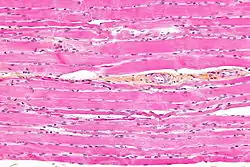

Striated muscle tissue is a muscle tissue that features repeating functional units called sarcomeres. The presence of sarcomeres manifests as a series of bands visible along the muscle fibers, which is responsible for the striated appearance observed in microscopic images of this tissue. There are two types of striated muscle: